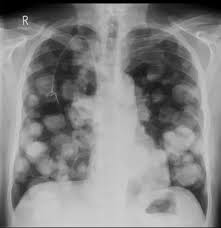

Common questions on breast cancer · what is breast 8. It can be slightly uncomfortable, basically they xray your breast in simple terms. Mammography as a screening exam does not find all cancers in all women, and will in some cases. Lung cancer chest xray films. What does lung cancer look like? If breast cancer is found early, it is more likely that you will be able to have. What does breast cancer look like? Each cancer type would look different on an mri, ct scan or pet scan.

· are there any vaccinations for cancer? What does lung cancer look like? Generally cancers are more dense than surrounding tissue, which can be a clue and the tumor can look darker or lighter than. What does breast cancer look like? Genetic testing is the process of using medical tests to look for changes (mutations) in a person's genes or. Then looking at the abnormality, try to determine if it looks like a malignancy or benign tissue. Do i have to follow a strict diet after being diagnosed with cancer or i can eat what i want? Any area that does not look like normal tissue is a possible cause for concern.

Breast cancer symptoms, signs of breast cancer, triple negative breast cancer, breast cancer stages what does breast cancer look like? Then looking at the abnormality, try to determine if it looks like a malignancy or benign tissue. Detects bone fractures, certain tumors and other abnormal masses, pneumonia, some types of injuries, calcifications, foreign objects. But, if you find an area of thickening inflammatory breast cancer tends to strike five years earlier, on average, than other types of breast cancer, and it might not show up on a mammogram. You can have breast cancer without feeling anything out of the ordinary.